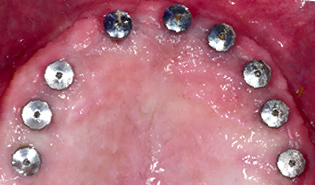

3.2 Immediate Load Prosthetics (All-on-4)

This part of the course covers the methods of diagnosis, practical treatment planning, pre-surgical prosthodontics, imaging, armamentarium, and clinical techniques needed for this exciting treatment modality. Crucial to this treatment modality is the understanding of the biomechanical aspects and functional loading of the immediate full arch prostheses. The aesthetic and phonetic requirements, space requirements, laboratory communication, insertion techniques post-operative follow-up and hygiene requirements are key to this treatment.

Presurgical prosthodontics

Understand the requirements and design of diagnostic and surgical templates